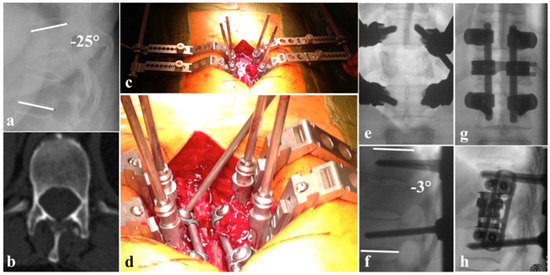

4. Posterior-Only Instrumentation

5. Two-Column Surgery